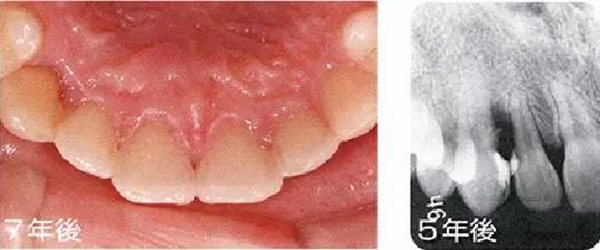

●埋伏齒矯正治療引起的附著喪失

15歲女性。對(duì)完全埋伏的右上尖牙進(jìn)行開(kāi)窗矯正使得牙齒崩出、整直。矯正結(jié)束后已出現(xiàn)7mm的牙周袋,并且有牙周出血現(xiàn)象,X片上也可觀察到骨吸收。推測(cè)是由于埋伏引起的偶發(fā)性附著喪失。有必要進(jìn)行徹底的控制,但在對(duì)患者進(jìn)行說(shuō)明后沒(méi)有獲得理解,中途放棄來(lái)院了。

主訴為其他部位而來(lái)院時(shí)拍攝的X片可觀察到,5年后和7年后的牙周袋雖然沒(méi)有大程度惡化,但依然有很深的牙周袋和出血現(xiàn)象。